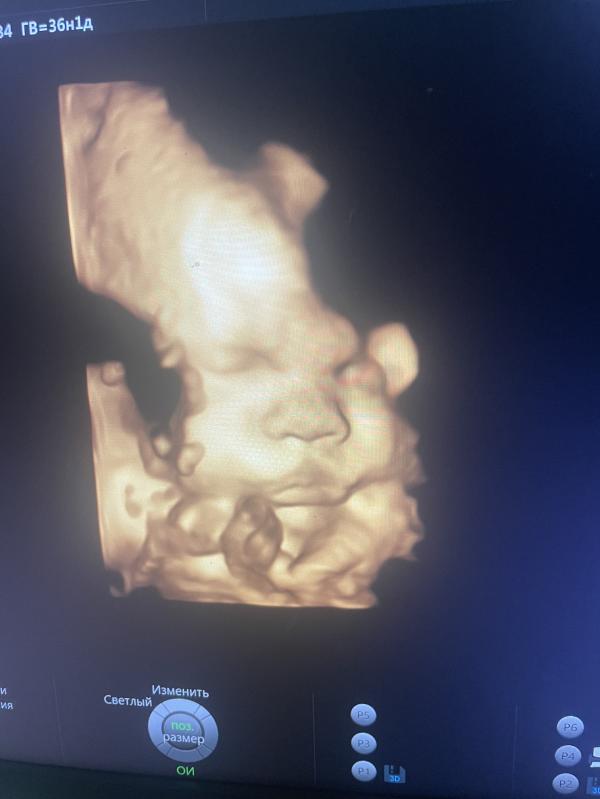

Была сегодня на узи) в целом все хорошо. Ждём 🙏🏻 однако… перспектива приближающихся родов пугает 🤭

Тоже такое узи делали, на видео увидели как зевает))))) это милота)))

У меня скажем так.. плановое . Так как гсд . И заодно показали вот )

@tverskaya это очень классно. Я платно пошла в 31 неделю, когда увидела, то счпсью не было предела, муж ещё видео снял, иногда пересматриваю))))